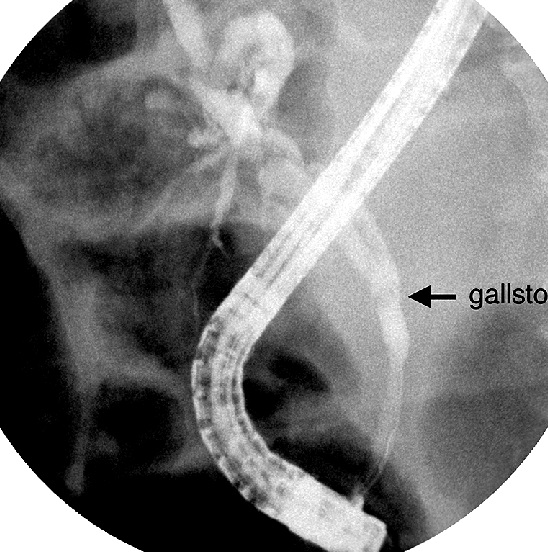

La

cholangio-pancreatographie retrograde (

ERCP ) : Methode reference pour localise et

caracteriser des calculs et des lesions obtructive du

choledoque . C'est une technique invasive qui se donne une

image tres nette de haute resolution . Cette technique se

permetre une geste therapeutique comme extraction des

calculs ou en place une Stein a la portion serre du canal

. Complication est perforation ,

hemorragie ou une pancreatite aigue

La ERCP

technique invasive pour explorer voie biliaire et

par cette voie on peut extraction de calcul ou en

place un stein pour s'etendre la portion serre |